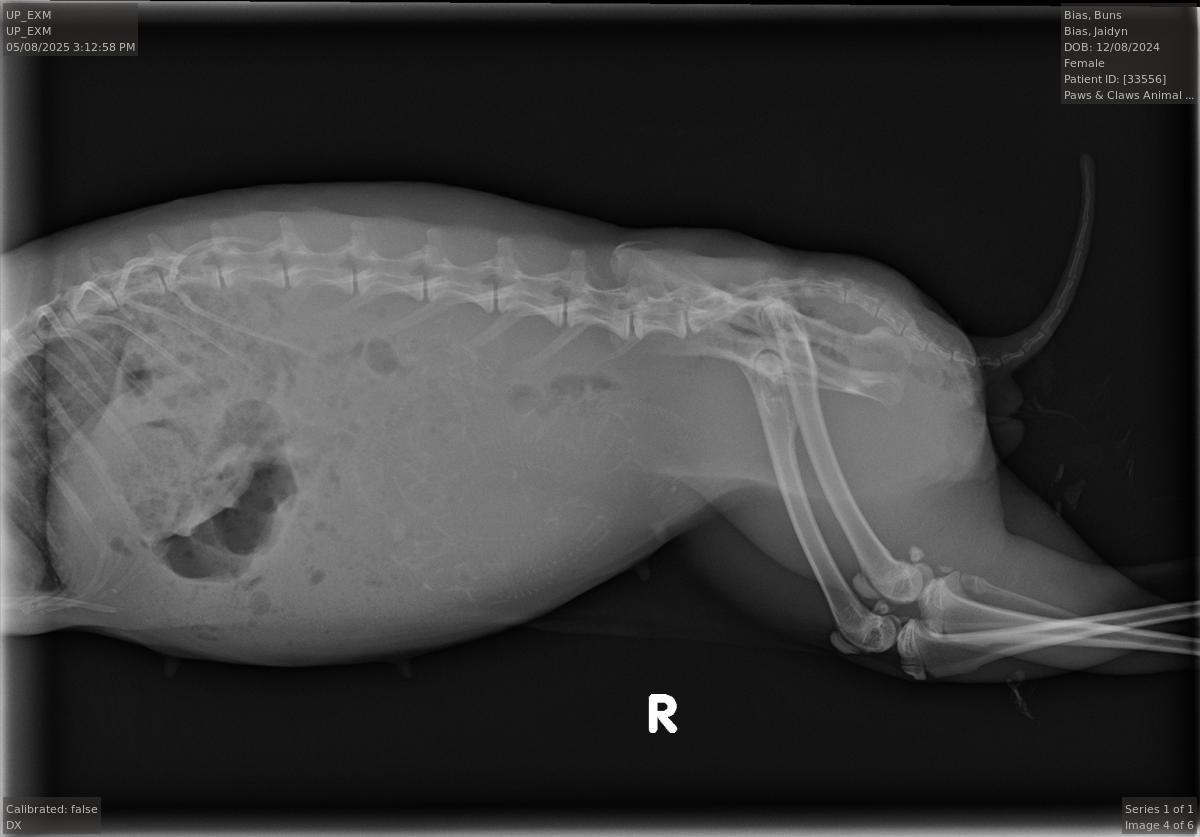

Hello, we are a couple of animal loving people who happened upon a pet bunny while on a walk with our dogs in our neighborhood. After taking the bunny to the vet (her name is Ms. Bunns), we found out that she was pregnant! I have experience with taking care of baby bunnies, and she is due any day to deliver her kits. We are requesting financial assistance to provide her kits with a safe and fostering environment before putting them up for adoption. Please donate today to help us with this most magical, unforeseen task of bringing new life into the world.